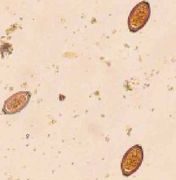

重度寄生を除いて症状をみることはほとんどない。豚の小腸に寄生する肥大吸虫は台湾、中国の中南部、インド、タイ、フィリピンなどに濃存します。虫体は腸粘膜に吸着し、局所の炎症、多数寄生の場合は潰瘍を生じ、腹痛、下痢、浮腫、貧血、腹水を発生し、稀に...